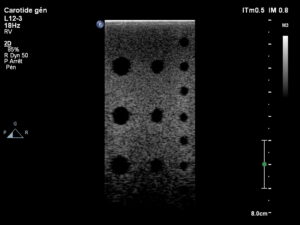

Après réparation du module acoustique

Après réparation